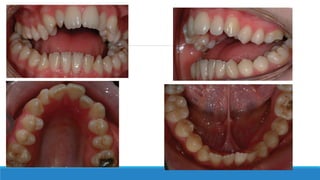

2. Pre-surgical Orthodontic

Pre-treatment Orthodontic decompensation After surgery